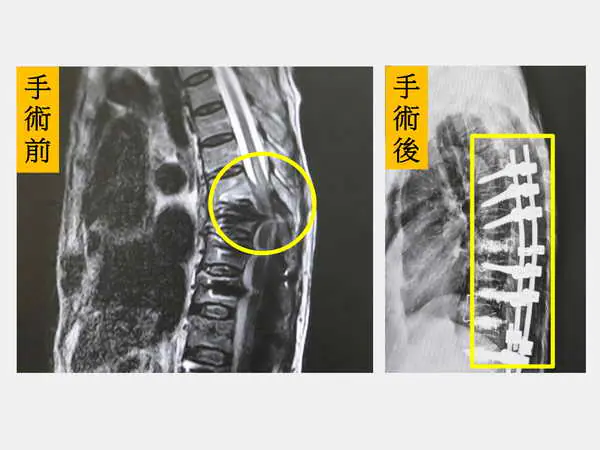

陳盈佑主任說,陳老太太過去接受的手術是從第八胸椎固定到整個腰椎,而這次發生的是第七胸椎爆裂性骨折壓迫到了脊髓造成雙腳癱瘓。除了進行脊椎板切除減壓外,也進行延長脊椎固定及後融合手術。

圖一:陳盈佑主任指出,陳老太太的第七胸椎發生爆裂性骨折且壓迫到脊髓,需緊急手術處理。

圖二:左圖,第七胸椎發生爆裂性骨折且壓迫到脊髓(圓圈處);右圖,完成脊椎長節手術(方框處)。